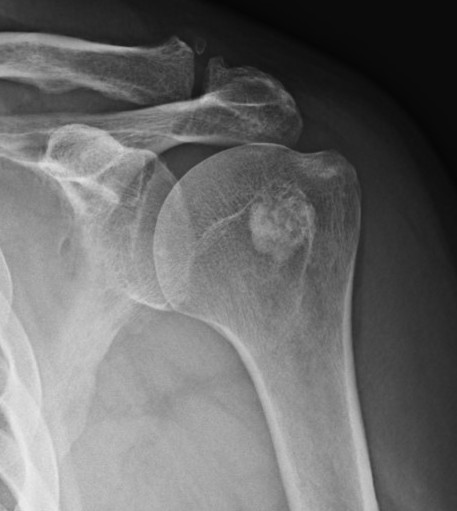

Osteopoikilosis

Rare inherited benign condition characterised by multiple bone islands

AD inheritance, high penetrance

Lesions clustered around joints

- typically arms, legs and pelvis

Malignant transformation extremely rare